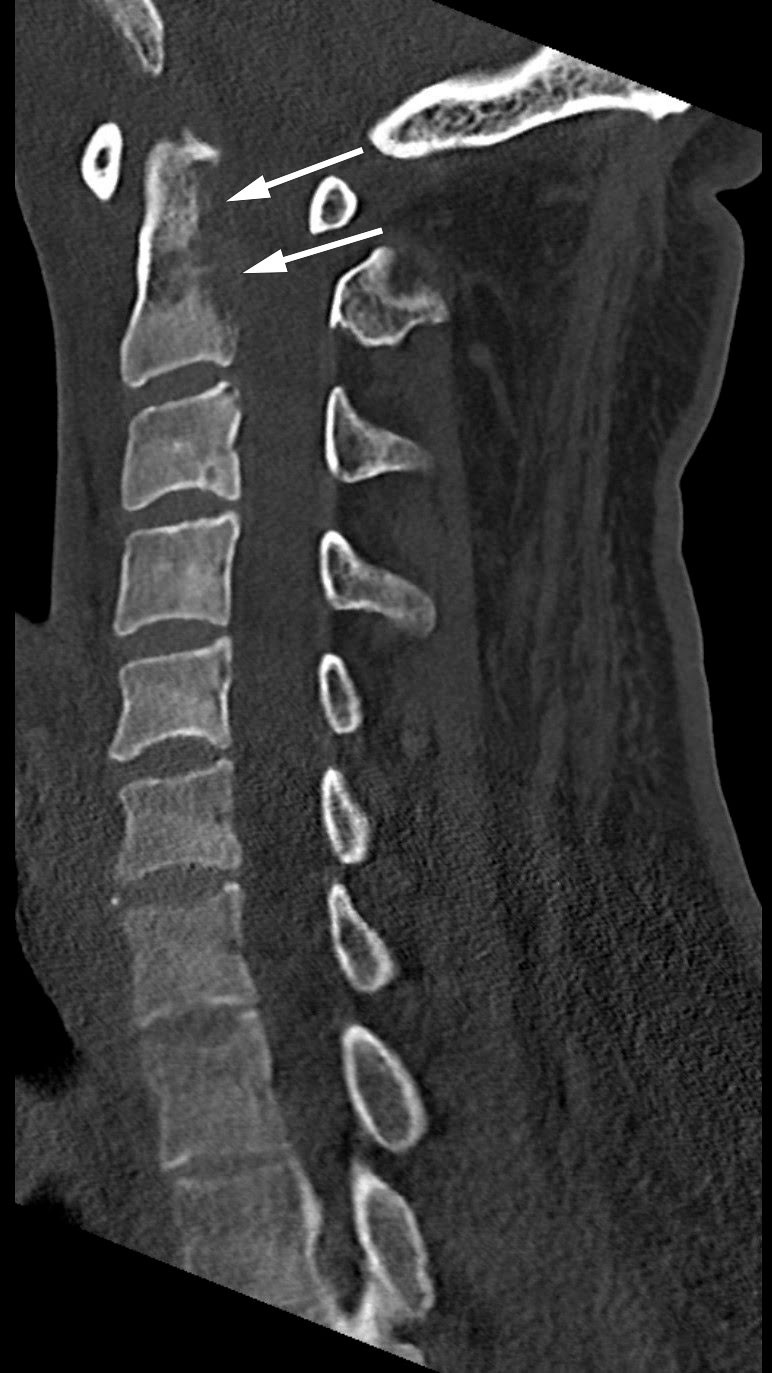

I påvente av poliklinisk MR-undersøkelse eskalerte pasientens kjente plager. Ca. seks måneder etter symptomdebut ble han lagt inn ved nyreseksjonen (dag 111). Ved innleggelse var han afebril, det ble funnet palpasjonsømhet og lett hevelse over C4–C5, og senkningsreaksjonen var fortsatt over 100 mm/t. Det ble rekvirert CT-undersøkelse av cervikalcolumna (figur 1), som ble utført samme dag. Denne viste osteolytiske forandringer i corpus av C2 og større deler av dens axis. Det var flere synlige lymfeknuter langs cervikalcolumna. Som bifunn fant man fortsatt fortetninger i mastoidalcellene bilateralt.

Etter anbefaling fra radiologene ble det gjort MR-undersøkelse av cervikalcolumna (dag 112). Denne viste osteolytisk lesjon posteriort i dens axis. Det var diffust margødem både i dens axis og i tilstøtende deler av C1, samt paravertebralt bløtvevsødem fra C1 til C5. I tillegg var det signalforandringer i clivus og venstre caput mandibulae, og tegn til synovitt i venstre kjeveledd.